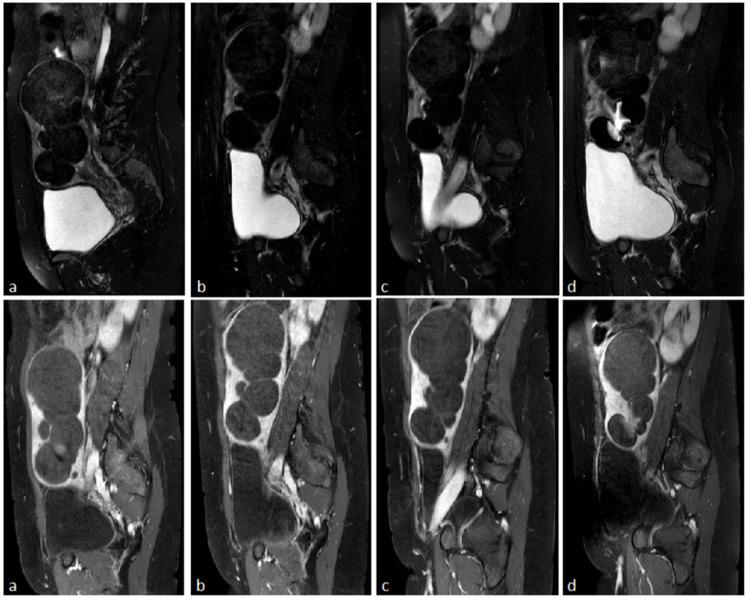

The patient presented symptoms of bloating and menorrhagia. Magnetic Resonance Imaging revealed uterine enlargement and elongation, with several fibroids and urinary bladder deformation caused by the enlarged uterus and the numerous fibroids compressing the uterine apex. She was referred for uterine artery embolization. In the three-year follow-up imaging, no alteration of the uterus' size was observed, while two fibroids were noted, suggesting necrosis or malignancy based on imaging findings, which led to the conduction of partial hysterectomy while leaving the cervix intact.

患者出现腹胀和月经过多的症状。磁共振成像显示子宫增大和伸长,有多个肌瘤,且因子宫增大和众多肌瘤压迫子宫顶端导致膀胱变形。她被转诊接受子宫动脉栓塞术。在三年的随访成像中,未观察到子宫大小有变化,但发现有两个肌瘤,根据成像结果提示有坏死或恶性病变,这导致在保留宫颈完整的情况下进行了部分子宫切除术。